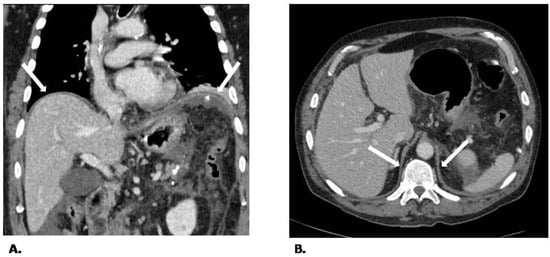

2.1. CT Protocol and Image Analysis

- Iochum, S.; Ludig, T.; Walter, F.; Sebbag, H.; Grosdidier, G.; Blum, A.G. Imaging of diaphragmatic injury: A diagnostic challenge? Radiographics 2002, 22, S103–S116. [Google Scholar] [CrossRef]

- Magu, S.; Agarwal, S.; Singla, S. Computed Tomography in the Evaluation of Diaphragmatic Hernia following Blunt Trauma. Indian J. Surg. 2012, 74, 288–293. [Google Scholar] [CrossRef] [PubMed]

- Jung, B.; Nougaret, S.; Conseil, M.; Coisel, Y.; Futier, E.; Chanques, G.; Molinari, N.; Lacampagne, A.; Matecki, S.; Jaber, S. Sepsis is associated with a preferential diaphragmatic atrophy: A critically ill patient study using tridimensional computed tomography. Anesthesiology 2014, 120, 1182–1191. [Google Scholar] [CrossRef] [PubMed]